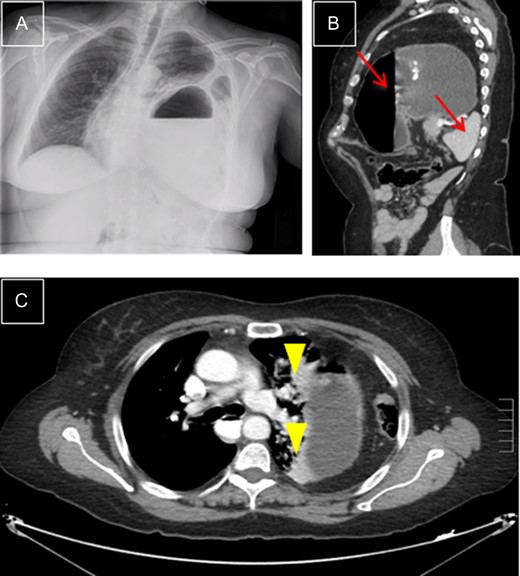

This is a 59-year-old woman. She underwent a left laparoscopic nephrectomy 4 years ago. She was admitted into the Emergency Department with anterior chest pain irradiated to the left shoulder changing with respiratory. The oxygen saturation was 90% and auscultation revealed a lack of breath sounds in the lower half of the left side of the chest. The abdomen was soft and not tender. The CT scan showed a large left diaphragmatic hernia, with intra-thoracic dilated stomach, spleen and descending colon, that led to the collapse of a large part of the left lung, with shifting of the mediastinum towards the right side of the chest (Fig. 2), not present in the pre-operative CT. An emergency laparotomy was performed, identifying a major left diaphragmatic defect, with herniation of the structures previously described that were reduced and performing a tension-free suture with interrupted stitches. There were no complications during the post-operative period. One year later, the patient is in good condition with no signs of recurrence.

Left diaphragmatic hernia. (A) Chest X-ray with visceral herniation in the chest and mediastinal shift. (B) CT, sagittal view with dilated stomach and spleen in left side of chest (arrows). (C) CT, transverse view: compressed lung parenchyma with atelectasis due to gastric compression (arrowheads).